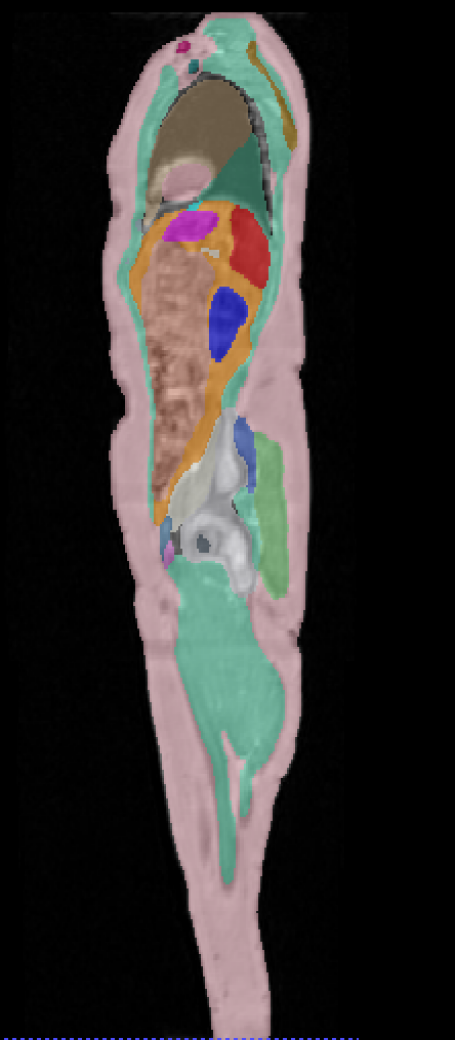

\captionof

figureUKBOB Size and Diversity. Our proposed UK Biobank Organs and Bones (UKBOB) is the largest labeled medical imaging dataset for segmentation, comprising body organs of 51,761 MRI 3D samples (17.9 M 2D images) and a total of more than 1.37 billion 2D masks of 72 organs. Left: we show label examples from UKBOB from axial, coronal, and sagittal views. Right: We show a plot of the size (number of 2D images) and diversity (number of classes) of our UKBOB compared to other medical images datasets. The size of the bubbles indicates 2D image resolution. This new scale in dataset size and diversity should unlock a new wave of applications and methods in the computer vision and medical imaging communities.